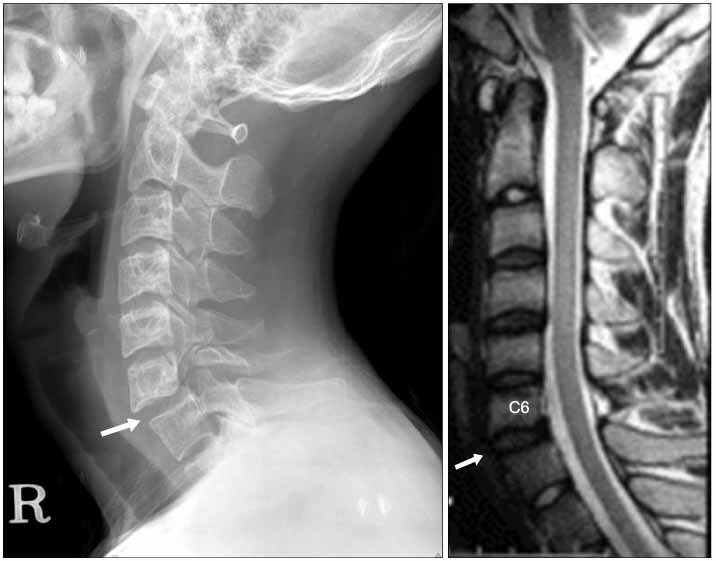

фото яндекс.картинок

Впервые проблемы со здоровьем произошли когда еще в детском саду спрыгнул с забора на прямые ноги, чтобы выиграть спор. Не могу понять, кто надоумил дворовых мальчишек брать на спор на такое, но у меня было смещение позвонков, неделю пролежал с подвешанным к шее грузиком. После этого запретили заниматься спортом, прыгать и так далее.